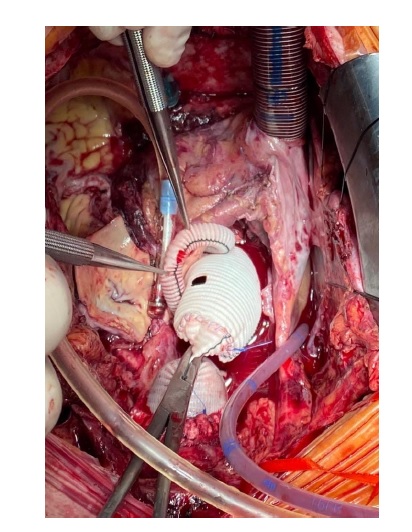

В нашем случае выбранная тактика связана с несколькими причинами: повторная операция, связанная с острым расслоением аорты, сочетание выраженного спаечного процесса с истонченными и рыхлыми тканями, значительная дилатация корня аорты. Протезирование устьев коронарных артерий выполнено по методике Cabrol протезом Vascutek № 6 с наложением анастомоза между сосудистыми протезами «бок-в бок» с целью минимизации травмы и рисков кровотечения в послеоперационном периоде (рисунок).

Рис. Операции Бенталла Де Боно с реимплантацией коронарных артерий по Сabrol